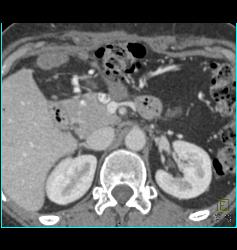

Diagnosis

1 Cm Islet Cell